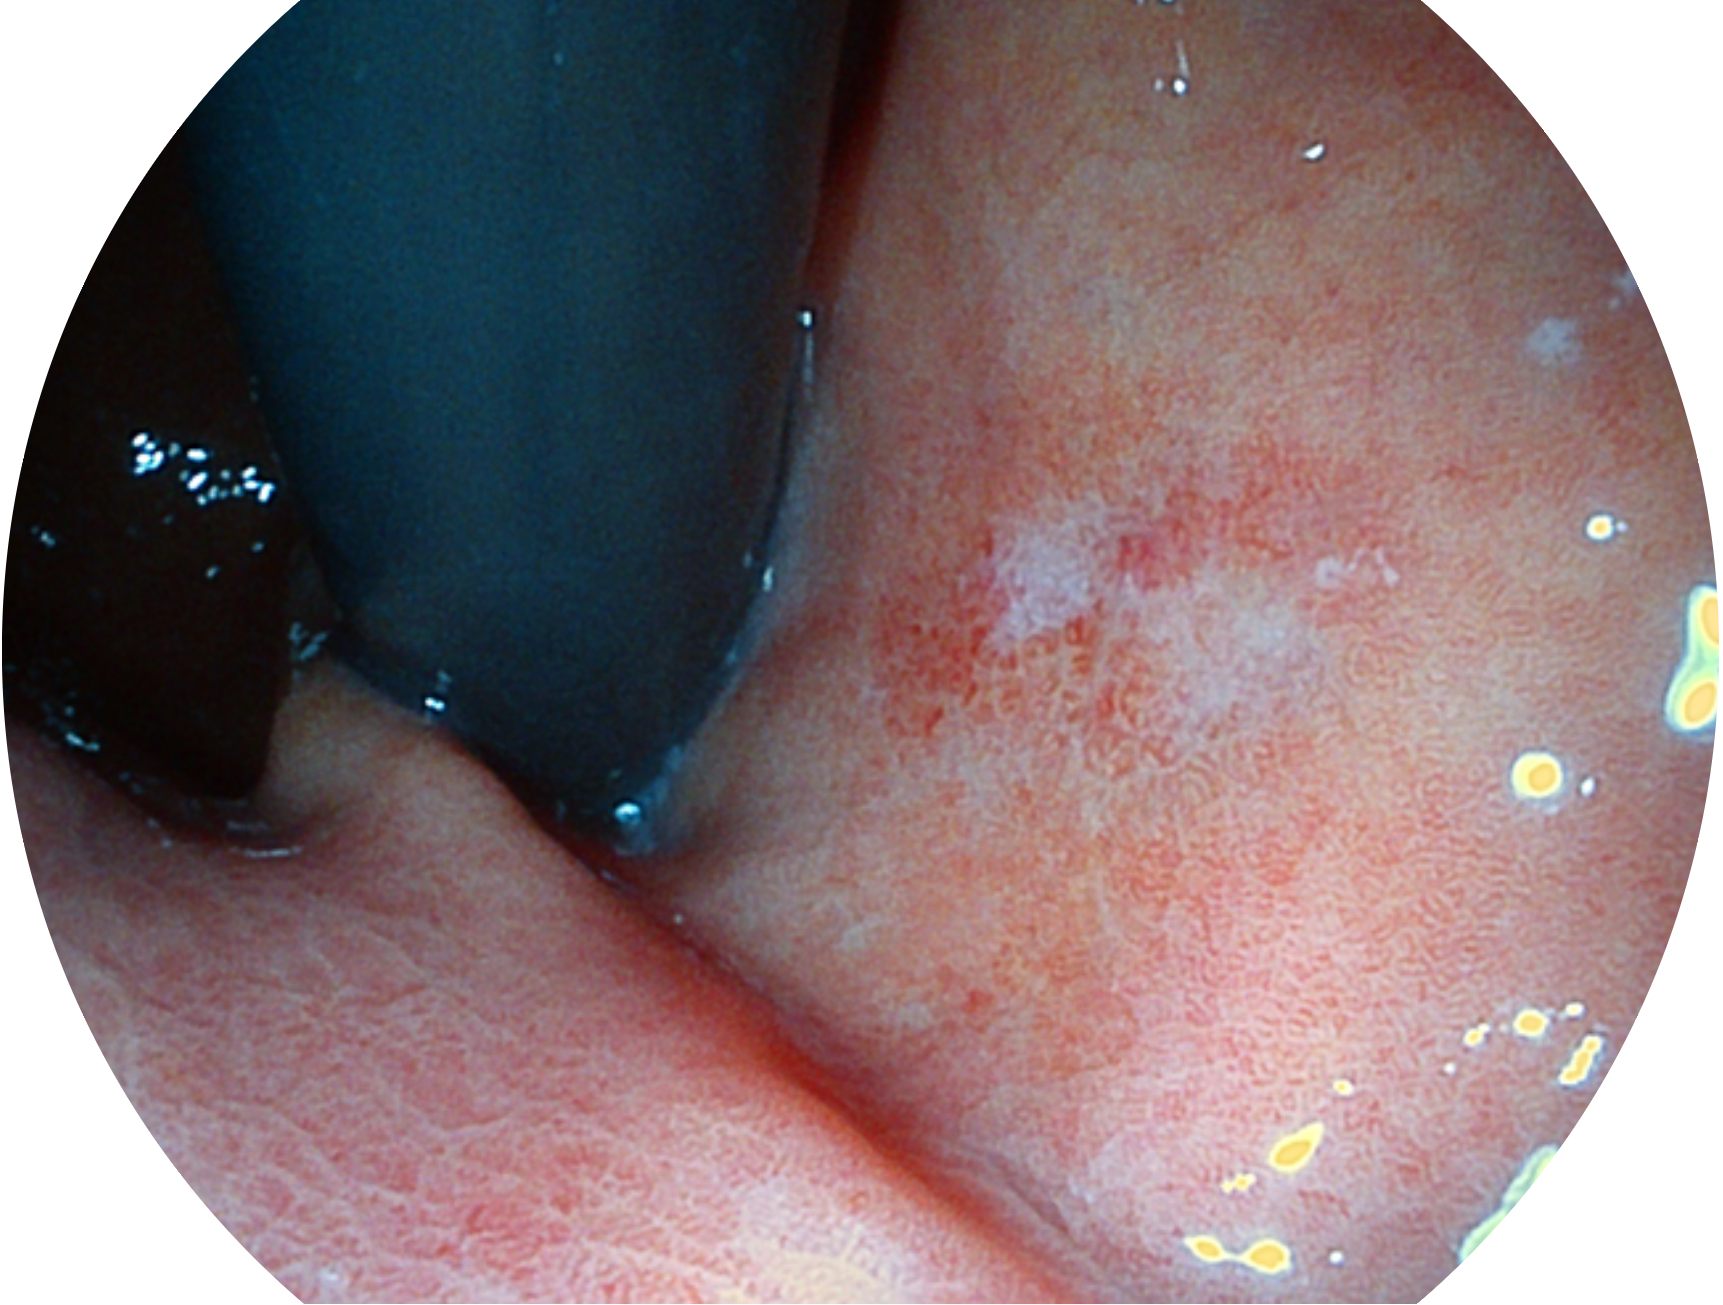

竞技宝(JJB)官方网站新开发的内镜染色技术,主要是基于多波长LED 光源的开发,VLS-55Q 四波长LED 光源是由四个不同颜色的LED光按照相应照明模式所规定的特定发光比例进行合束后形成,合束后形成的照明光的光谱由红光、绿光、蓝光及蓝紫光这四个不同的波段范围构成。具有更高光谱自由度,通过光谱比例的控制,实现了聚谱成像技术,英文全称为“Spectral Focused Imaging, SFI”,缩写为“SFI”和光电复合染色成像技术,英文全称为“Versatile Intelligent Staining Technology, VIST”,缩写为“VIST”。